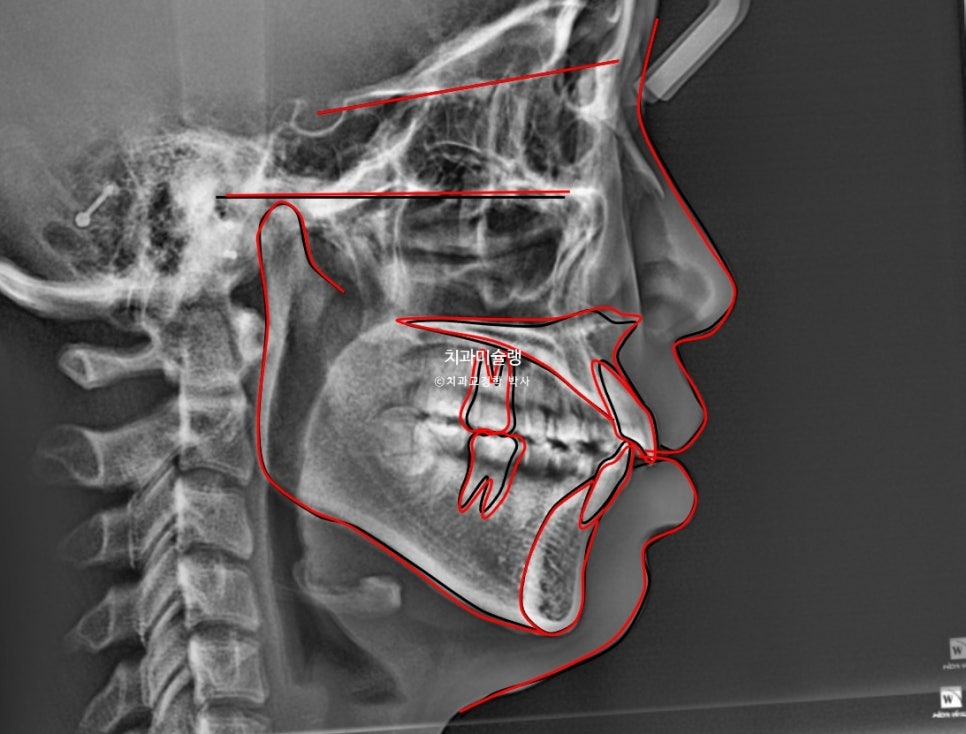

본원에 과거 4월 교정 전 엑스레이 자료가 있어 현재 11월 상태와 객관적으로 중첩을 해보았습니다.

까만선이 24년 4월 초진, 빨간선이 24년 11월 입니다.

2급 고무줄을 끼면서 위 앞니와 어금니를 포함한 전체치열이 뒤로 소량 들어가고 아래 전체치열은 앞으로 소량 나온것이 확인됩니다.

과개교합이라도 먼저 해결을 한 후 2급 고무줄을 꼈다면 모를까, 과개교합 개선이 안된 상태에서 이러한 치아이동은 앞니에 더 심한 교합간섭을 만들고 다물때 아래턱이 뒤로 밀리는 증상이 생길 수 밖에 없죠. 아래턱이 뒤로 밀리면 관절공간을 압박하여 턱관절 통증이 생길 수 있습니다.

교정 전후 옆 엑스레이 중첩입니다.

앞니 돌출이 해소되며 입술이 한결 편하게 다물립니다.

뒤로 밀렸던 턱이

과개교합이 해소되면서 소량 앞으로 나왔습니다.